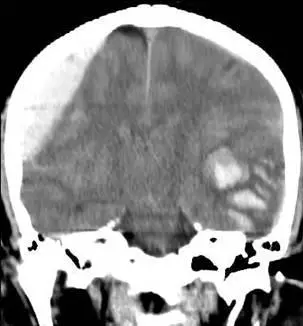

從 coronal 無對比腦部 CT 可見:

- 影像左側(病人右側)沿顱骨內板貼附一塊均質高密度、雙凸(biconvex)之出血,內側邊緣光滑向腦實質凸出,未沿縫線延伸,可見明顯質量效應與正中結構左偏,典型急性 epidural hematoma (saem.org)。

- 影像右側(病人左側)大腦皮質下呈現多發混雜高密度斑點,周邊伴低密度水腫,呈「salt-and-pepper」外觀,符合 traumatic cerebral contusion 併 intraparenchymal hematoma (clinicalgate.com)。

- 明顯 midline shift,若持續進展將引發單側散大瞳孔(第三腦神經受壓)及顱內壓急升。

影像明確顯示病人右側為典型 epidural hematoma、左側為 contused intracerebral hematoma;選項A將左右側病變對調,因此為唯一錯誤敘述,為本題正確答案。